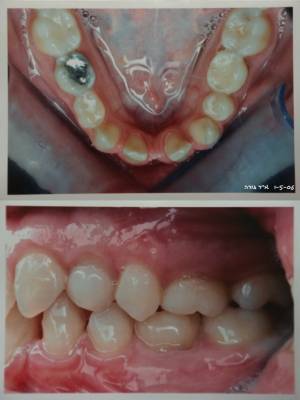

jeune fille de 19 ans avec agenesies:

(18)15,12,22,25(28)

(48)45,42,32,34,35

motivation esthetique(espaces!) renforcee par la soudaine mobilite des canines sup deciduelles

jusqu'a maintenant on lui a dit d'attendre 18 ans pour penser aux implants